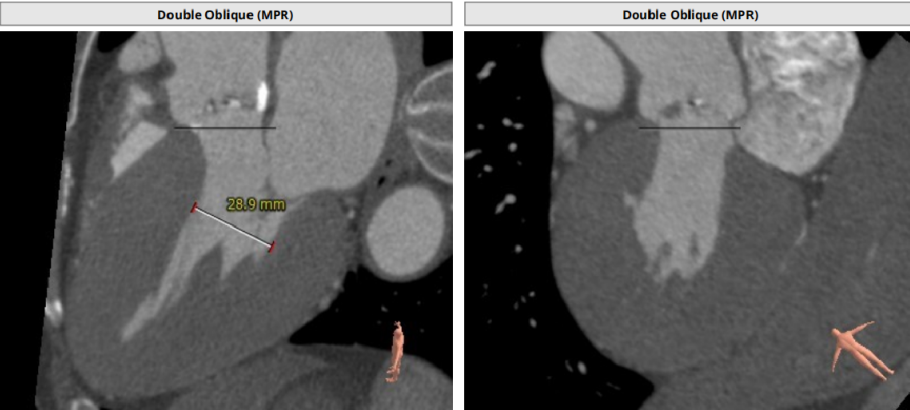

CT分析

Anulus 25.7、LVOT 23.7;STJ高度可,窦部空间足够;初步预估29/32瓣膜。

升主未见增宽,角度尚可,轻度钙化。

左右冠高度不低,球扩体位:LAO 26、CRA 18;释放体位:LAO 9、CRA 4;心室腔略小。

入路直径足够,分叉点足够高。右股作为主入路。